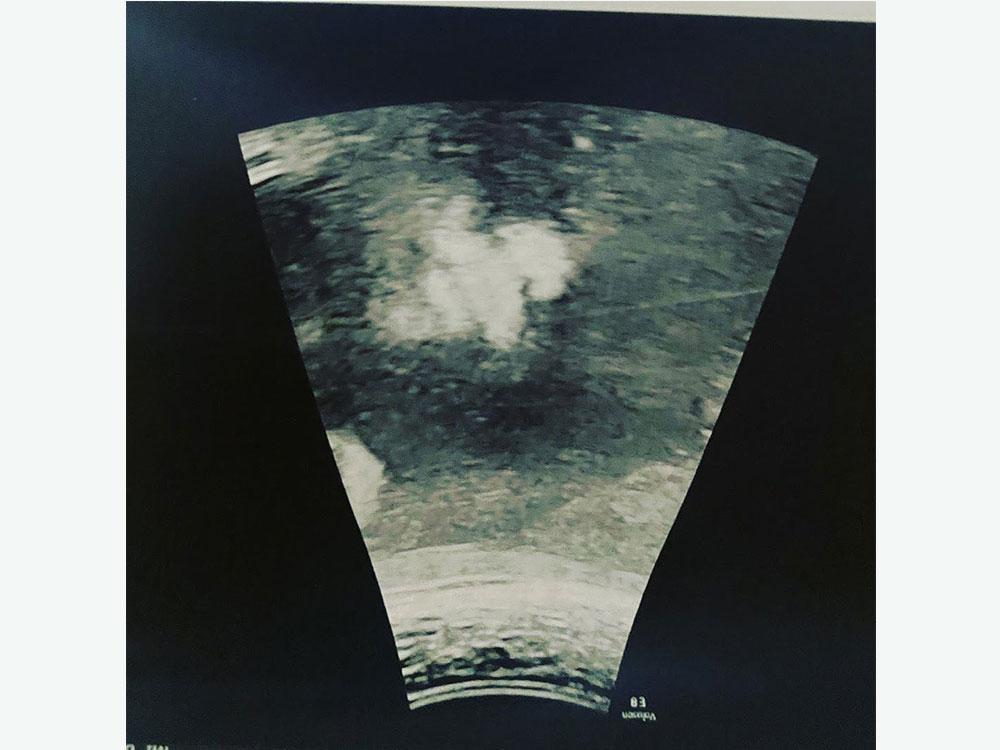

Ultrasound